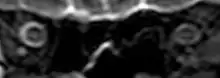

On 2 November 2017, scientists reported that significant changes in the position and structure of the brain have been found in astronauts who have taken trips in space, based on magnetic resonance imaging (MRI) studies. Astronauts who took longer space trips were associated with greater brain changes.[11][12]